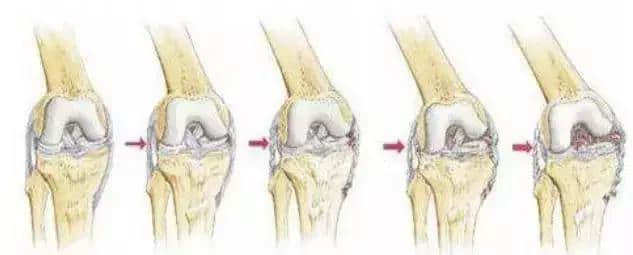

关节内的骨软骨病,病因不明,关节软骨和软骨下骨变性和再钙化,最常见于股骨内髁,模糊的、定位不清的膝关节疼痛,有晨僵,反复的关节内积液(轻度)。如有游离体,可发生交锁症状。股四头肌萎缩,受累股骨髁关节软骨面压痛。X线平片显示骨软骨病损或关节内游离体。如怀疑剥脱性骨软骨炎,摄片应包括前后位、后前隧道位、侧位和髌股关节切线位。